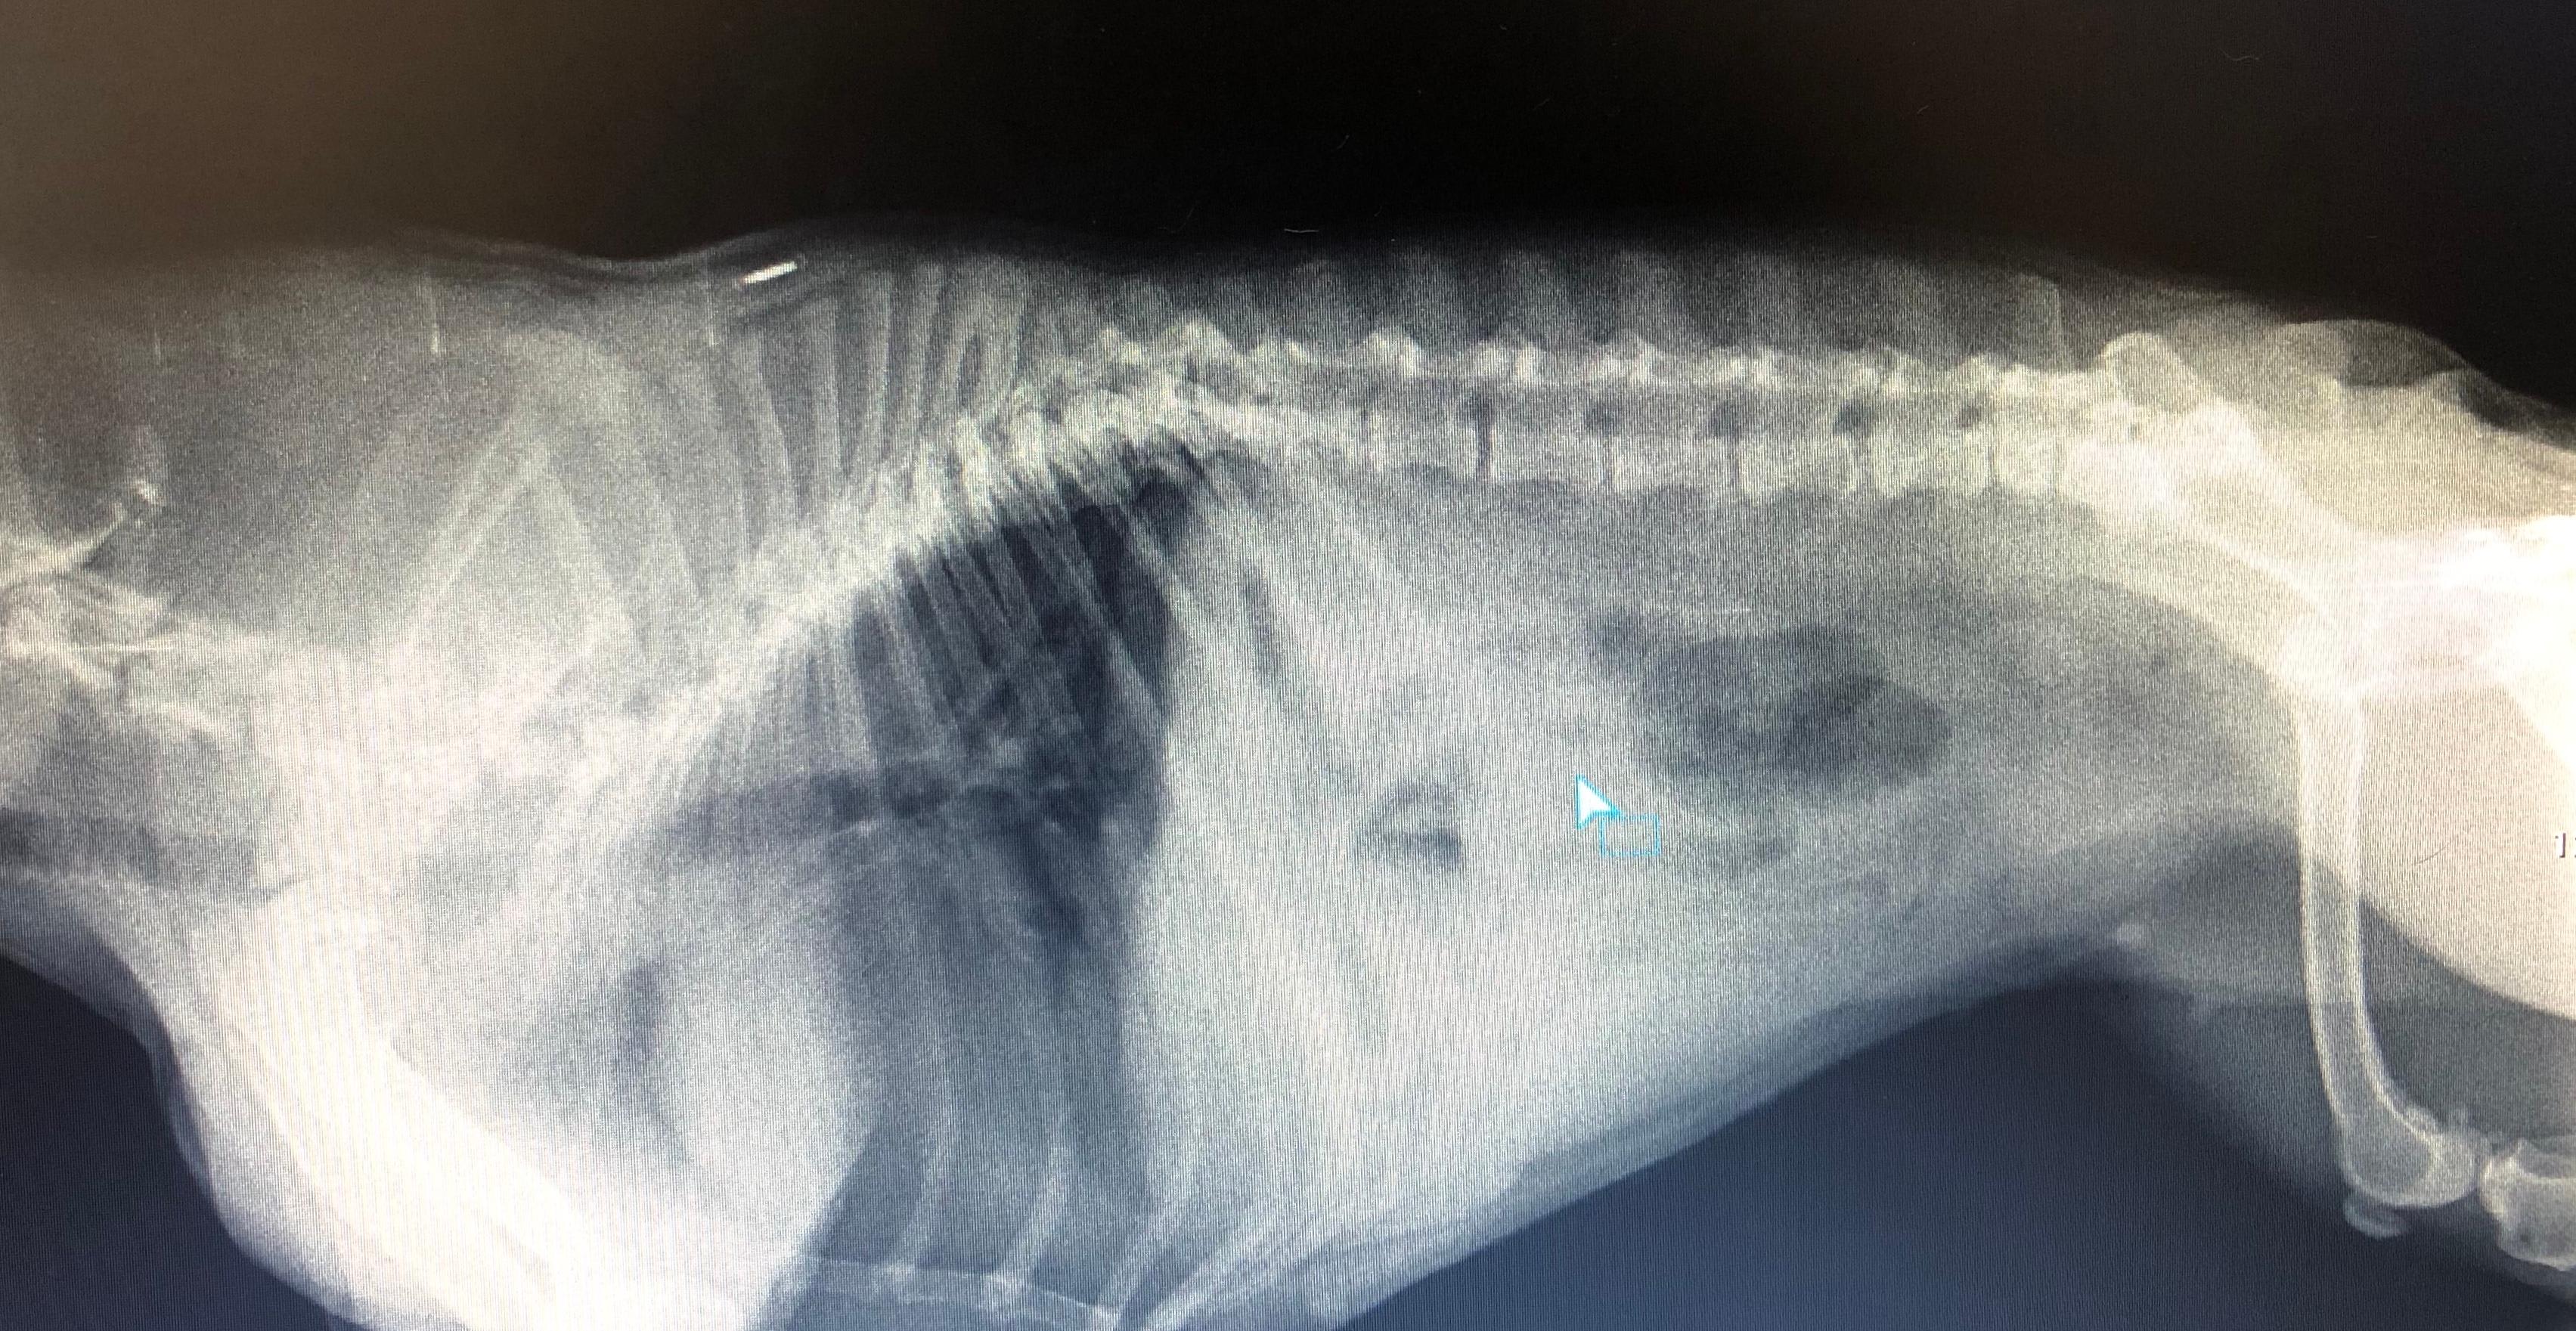

Hi, I have a 4-year-old French bulldog that was in pain a few days ago. She was diagnosed with spondyloarthrosis and I was told that there is really not much that can be done but treat her for pain management and reduce her physical activity. I live in a small town and there is no one else that I can go to for a second opinion. I hereby attach the radiography and hope that you can take a look. Thanks!

Hello, sorry to hear about Sasha. She does indeed have some changes in her spin consistent with spondylosis deformans. However, another potential cause of her back pain could include a herniated disk also known as Intervertebral Disk Disease. This can be a very painful condition and cause patients to have nerve deficits, back pain, and become unable to walk. Rest and pain medication will help in about 30-40% of the cases of dogs whom are not able to walk. In. dogs who still are able to walk, they may recover with strict rest and medical management. Strict rest should be instituted for at minimum of 4 weeks with no running, jumping, or rough housing to be allowed. If Sasha does not improve, her pain seems worse or if she is unable to walk, then she needs to be evaluated by your veterinarian or even a neurologist. Please contact your veterinarian to have her evaluated. Hope this helps and best of luck.